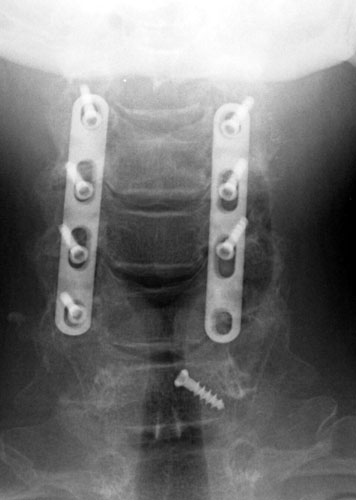

AP and lateral radiographs taken 5 days later, while still in the

hospital. Note migration of left C6 screw. It has loosened and fallen out. This

screw was not causing symptoms and decision was made to conservatively manage

the patient and keep in rigid cervical collar until the bone graft matured in

2-3 months. |